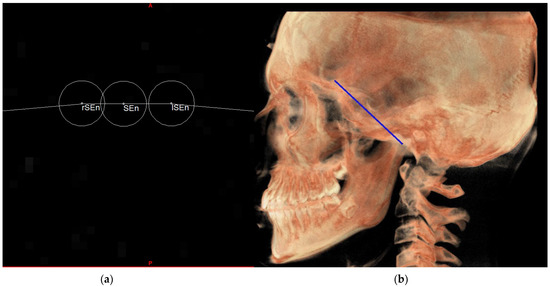

| SE neutral (SEn) | / | Point of a circumference with center in Ba and radius equal to MCFx, in which an angle of the skull base equal to 40.3° is obtained | / |

| Right SE neutral (rSEn) | / | Point taken arbitrarily on the right side of the SEn on the same arc of circumference | / |

| Left SE neutral (lSEn) | / | Point taken arbitrarily on the left side of the SEn on the same arc of circumference | / |

| Middle point MCF (MCFx) | / | Point of intersection between the plane on which the Ba lies and a line joining the left and right MCF | / |

| MCF neutral (MCFn) | Plane passing through the Ba, rSEn and lSEn which forms an angle of 40.3° with the PMn at the SEn point |